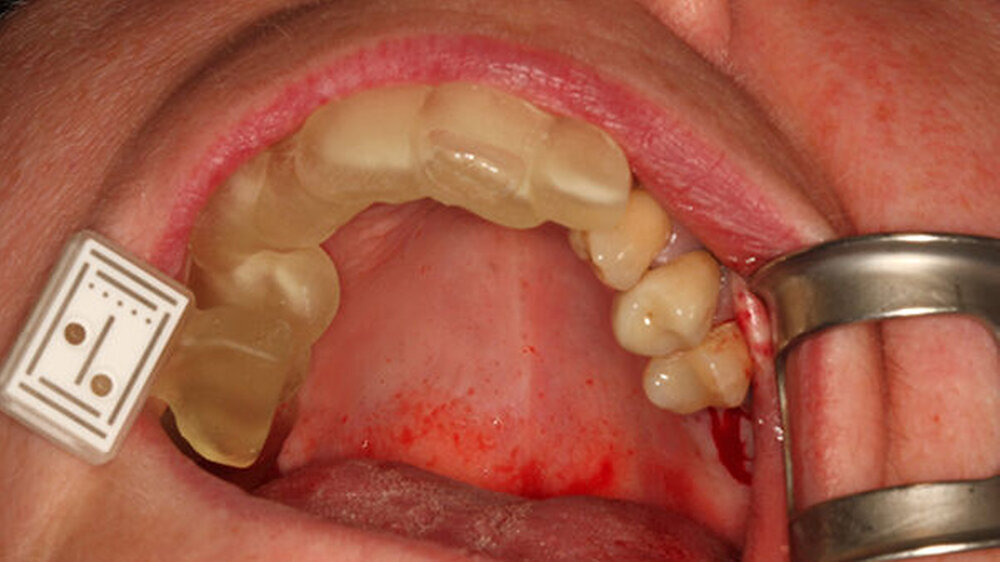

Digital erstellte Gaumenplatte für den Kiefer eines Neugeborenen

Das Tübinger Team behandelt regelmäßig mittels digitalem Workflow erstellter Behandlungsapparaturen Neugeborene und Kleinkinder, welche an angeborenen kraniofazialen Fehlbildungen leiden.

Im interdisziplinären Team von Neonatologie und Kieferorthopädie wurde das schonende Behandlungskonzept der „Tübinger Gaumenplatte“ (TPP, Tübingen palatal plate) genutzt, um invasive Therapieoptionen zu vermeiden. Bei der TPP wird eine spezielle Gaumenplatte mit velarer Extension in Mundhöhle und Pharynx eingeführt; diese wirkt der Obstruktion der oberen Atemwege entgegen, indem sie den Zungengrund nach vorn drückt.

Mittels einer Endoskopie wurden weitere Ursachen einer Atmungsstörung ausgeschlossen, wobei gleichzeitig Form und Größe des Plattensporns am additiv gefertigten Prototypen überprüft wurden. Mit einem Intraoralscanner wurden im Oberkiefer die Daten für die Gaumenplatte gewonnen. Durch deren Konstruktion wirkt sie der Verengung der Atemwege entgegen (Abbildungen 3, 4).

Mit dem digitalen Workflow konnten verschiedene Konfigurationen der Gaumenplatte entworfen und das passende Design in der Fertigung umgesetzt werden. Inkorporiert wird die Gaumenplatte vier bis sechs Monate getragen.

Konventionelle Alginat- oder Silikonabformungen hingegen zeigen sich aufgrund der Gefahr von Aspiration und Verbleib von Abformmaterialresten als komplikationsreicher und sind daher für diese Therapie in Anbetracht des Lebensalters der kleinen Patienten schlechter geeignet. Die digitale Intraoralabformung wird in Tübingen auch bei Lippen-Kiefer-Gaumenspalte und Trisomie 21 (Down-Syndrom) standardmäßig erfolgreich für die Erstellung von Apparaturen eingesetzt.